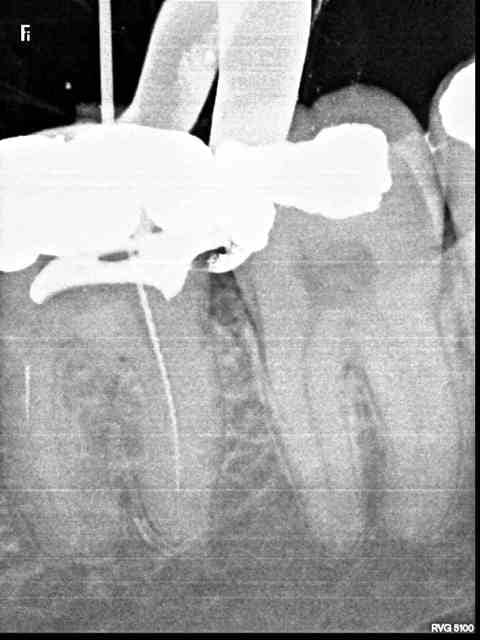

Canal MV au milieu c'est quoi cette connerie?

pas vu, peut etre un bout de thermocompacteur mais il me semble un peu petit sinon superposition des deux canaux? demain je te mats l'autre radio avec une autre incidence je regarderai, mais toute façon pas grave du tout (sauf pour mon instrument)